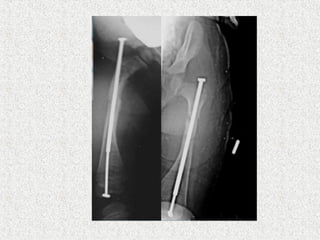

ļ‚ž Sofield & Millar

ļ‚” Multiple osteotomies

ļ‚” Realignment

ļ‚” Medullary nail-solid

ļ‚ž Indication

ļ‚” Deformity correction

ļ‚” Prophylaxis

ļ‚ž 4 main types are developed

ļ‚”Bailey-Dubow

ļ‚”Sheffield

ļ‚”Fassier-Duval

ļ‚”Interlocking telescoping rods

ļ‚ž These rods have a female hollow nail anchored

in the proximal epiphysis of the long bone and a

male solid nail anchored to the distal epiphysis.

They are elongated as the child grow. So, less

revision rates compared to solid